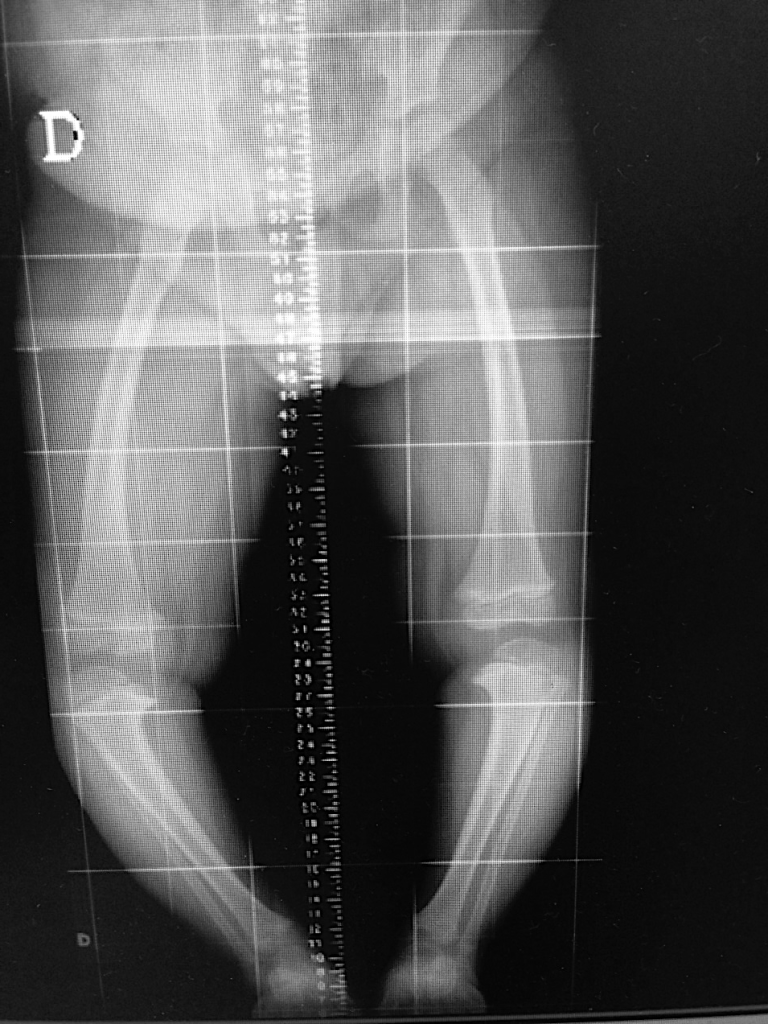

Estudos radiográficos podem auxiliar o médico a avaliar a forma dos membros, registrá-los para comparação futura durante o crescimento, estudar defeitos ósseos ou articulares, com correspondência a várias doenças que podem causar tais alterações (figuras 3 A e 3 B).

Figura 4. Joelhos varos por doença hereditária (Blount).